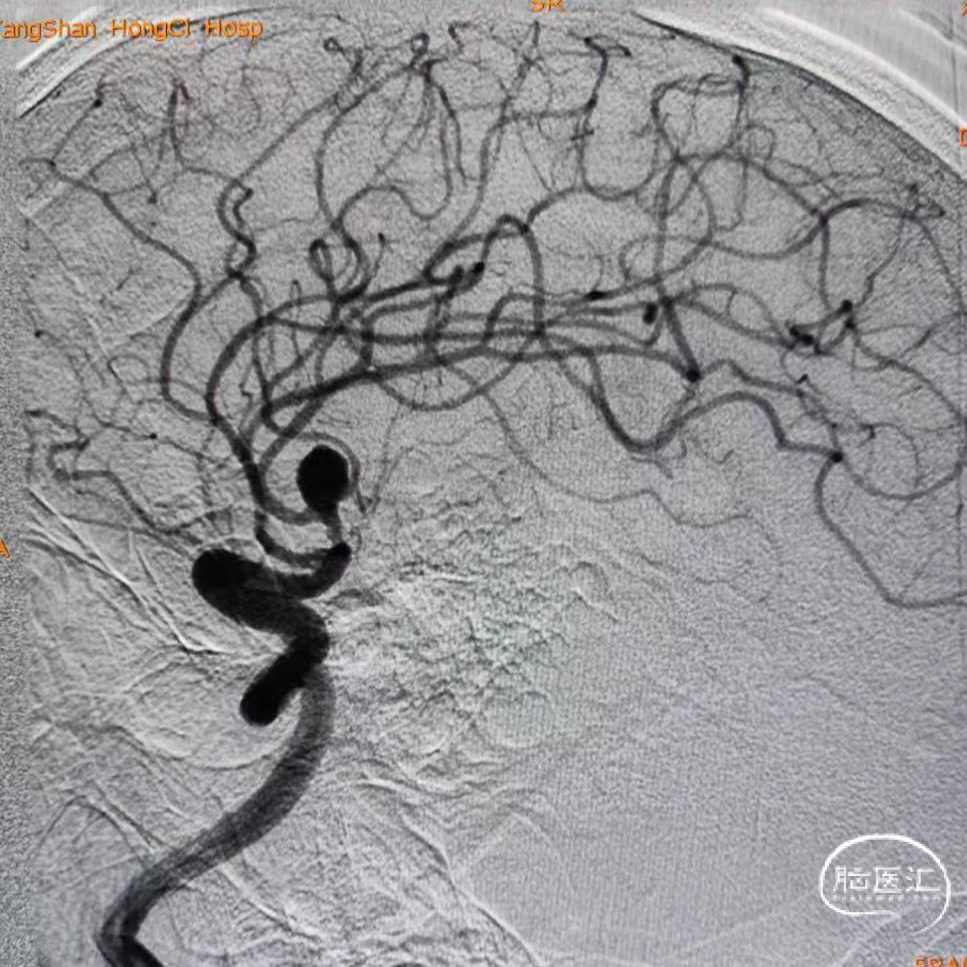

脑血管造影显示右侧大脑中动脉分叉部宽颈动脉瘤,约7.4-7.0-6mm大小。动脉瘤为不规则形态,右侧中动脉上下支干均受累,其中上支干纤细约1.0mm,自瘤体近瘤颈处发出。

术前影像

手术方案